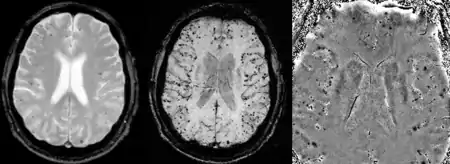

Gradient recalled echo (GRE) imaging is the conventional way to detect hemorrhage in CAA, however SWI is a much more sensitive technique that can reveal many micro-hemorrhages that are missed on GRE images.[7] A conventional gradient echo T2*-weighted image (left, TE=20 ms) shows some low-signal foci associated with CAA. On the other hand, an SWI image (center, with a resolution of 0.5 mm x 0.5 mm x 2.0 mm, projected over 8mm) shows many more associated low-signal foci. Phase images were used to enhance the effect of the local hemosiderin build-up. An example phase image (right) with yet higher resolution of 0.25 mm x 0.25 mm x 2.0 mm shows a clear ability to localize multiple CAA-associated foci.